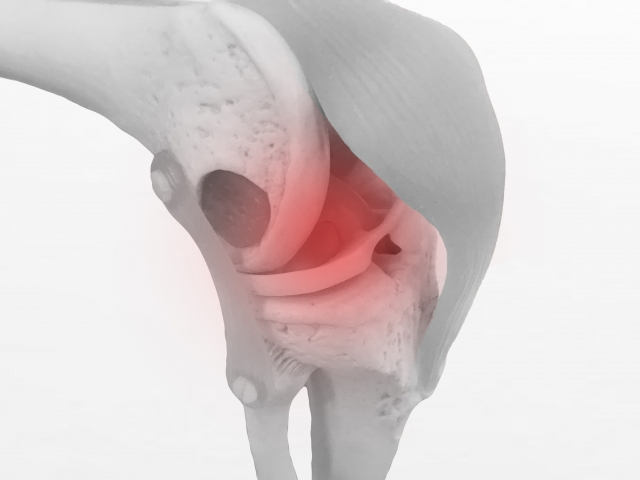

日常生活やスポーツ活動において、「膝のねじれ」や「姿勢の崩れ」を感じる方は少なくありません。こうした関節のアライメント(骨や関節の位置関係)の乱れは、身体の動かし方のクセや筋肉の働き方の不均衡から生じることがあります。特に膝関節は構造的に不安定な部位であり、アライメントが崩れることで負担が集中しやすい場所です。

本研究では、膝関節の「内反角度(いわゆるニーイン)」が大きい女性アスリート28名が対象となりました。膝の内反角度が強い状態は、スポーツ中に膝へ過剰なストレスをかける要因とされ、傷害リスクの高さとも関連すると言われています。

• 単脚ジャンプ動作における膝の内反角度が平均で約6度減少

股関節や足関節周囲の筋が適切に働くことで、膝への不要なストレスが軽減される可能性があります。

長期的に見れば、膝や腰などの関節への負担が減り、不調や障害の予防に役立つと考えられます。